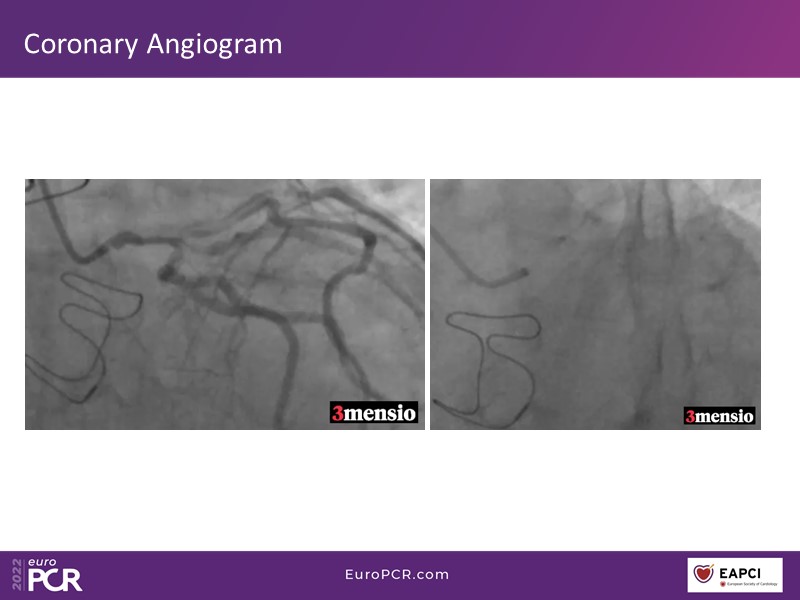

Through the presentation of real-life clinical cases, this session will allow you to discover the use of ALLEGRA for valve-in-valve TAVI, understand the management of coronary artery disease in TAVI patients, better detect when and how to protect coronary arteries during TAVI, or even learn how to perform commissural alignment with ALLEGRA.

- To understand the management of coronary artery disease in patients undergoing TAVI

- To better detect when and how to protect the coronary arteries during TAVI